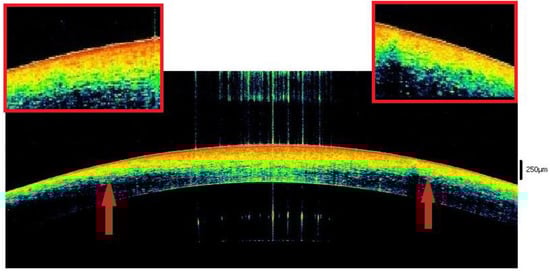

- Homogeneity and preservation of the physiological structure of the corneal stroma. The presence of alphabetic-shaped stromal striae (SS) was osservable in a variable (Figure 2) number of cases.

| 3–6 | Lacrimal tear progressively disappears. Hyperreflectivity with a “binary” pattern. | Initial thinning with differentiation between the anterior (hyper-reflective) and posterior (hypo-reflective) parts. | Hyper-reflective whit spots. | Initial sawtooth and stromal striae are detectable in the stroma. |

| 6–9 | Single, hyperreflective layer. | Decrease in stromal thickness. Hyperreflectivity in ¾ of anterior tissue in 68.5% of cases. | Unchanged. | Unchanged |

| 9–12 | Unchanged | Hyperreflectivity reaches the endothelium and takes a trapezoid form. | Enhancing of hyperreflectivity. | Stromal striae (65.8%) Sawtooth sign (78,2%) Initial loosing of the spheric form of the tissue in 21.7% of cases |

| 12–17 | Unchanged | Rising of posterior stroma hypo-reflectivity that in some cases reaches the middle of the tissue. | Are evident areas of hypo-reflectivity. | Stromal striae (100%) Sawtooth sign (100%) Initial loosing of the spheric form of the tissue in 34.7% of cases |